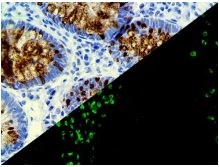

Bio SB has developed a highly sensitive Immunofluorescence and non-biotin monovalent Fab micropolymer IHC detection systems for the detection of IVD antibodies for Complement (C1q, C3c, C3d, C4c, C4d), Serum Proteins (Albumin and Fibrinogen) and Immunoglobulins (IgA, IgD, IgE, IgG, IgM, Kappa and Lambda) related to autoimmune conditions. Our innovative IF and IHC detection systems and high affinity antibodies, have opened the doors for a faster and accurate Immunofluorescence and Immunohistochemistry applicable to Autoimmune Disease like Nephropathies and Lupus.

These antibodies and detection systems are intended for use in Immunohistochemical (IHC) and Immunofluorescence (IF) applications of formalin-fixed paraffin-embedded tissues (FFPE), frozen tissue sections and cell preparations.

InDirect Immunofluorescence Detection

Rabbit FluoroDetector FITC |

Rabbit FluoroDetector FITC with FluoroMounter |

Rabbit FluoroDetector FITC with FluoroMounter with DAPI |